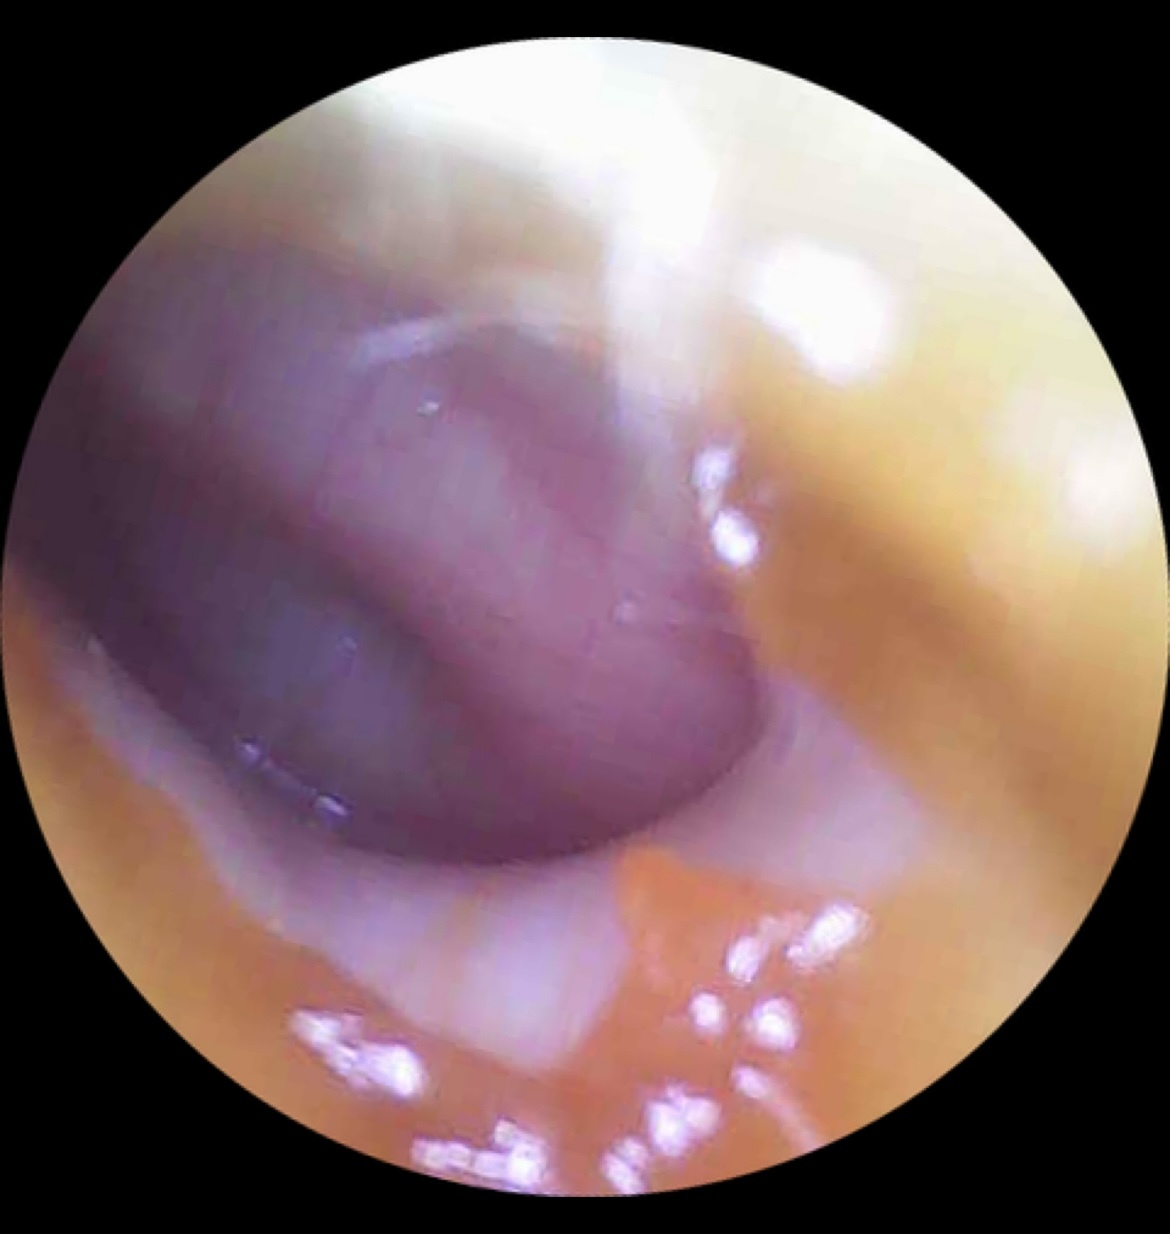

Острый гнойный средний отит ( тот самый, когда как раз нужны антибиотики)

Острый катаральный средний отит. Не требующий антибиотиков! Даже если болит. Антибиотики - не обезболивающее. Нужно бдительное наблюдение и врач на связи.

Экссудативный средний отит. Скопление НЕгнойной жидкости в ухе. Бывает после гнойного отита, на фоне долгих насморков и потому что потому.